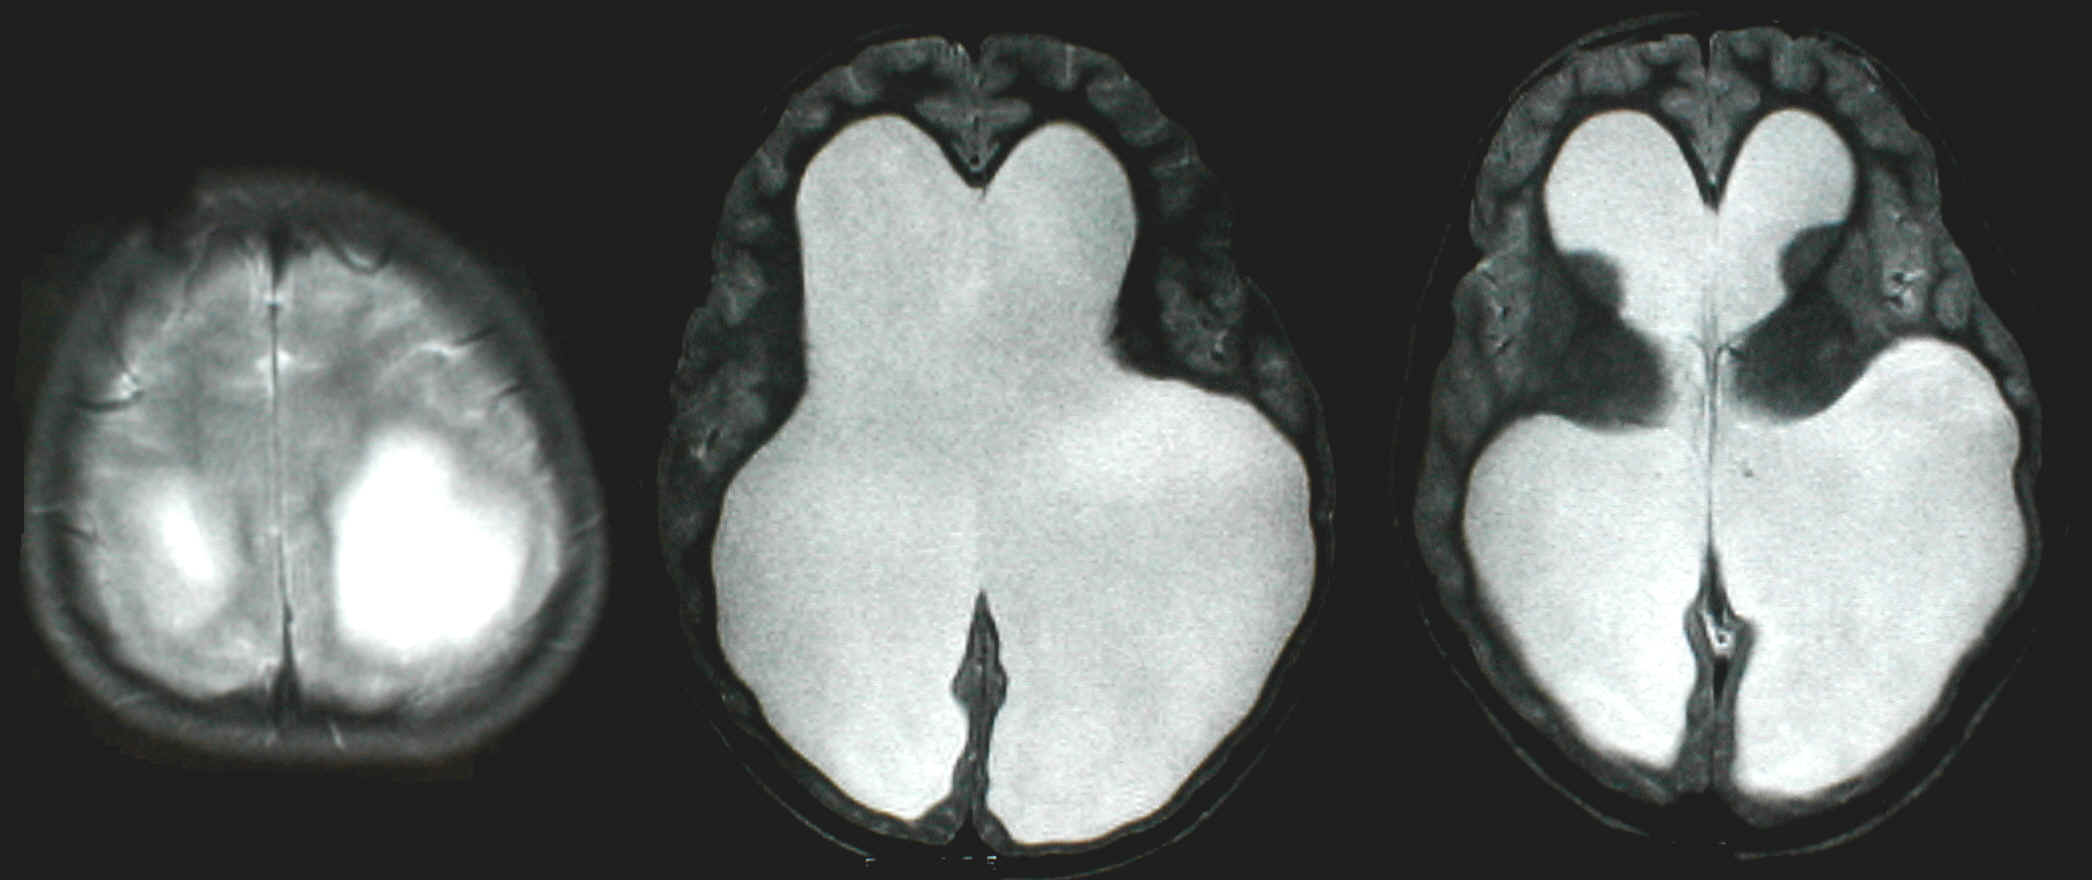

T2-gewichtetes Kernspinbild bei LOVA: alles was weiß ist ist Seitenventrikel im Großhirn, die hell- und dunkelgrauen Strukturen sind das verbliebene Gehirn, es ist insbesondere im Hinterhauptsbereich nicht mehr dicker als 5 mm. Dennoch: Die Patientin kann nach Therapie jetzt ein völlig normales Leben führen und ist voll berufstätig nachdem sie ihr Abitur geschafft hatte (Motto: die absolute Masse macht's nicht unbedingt, sondern das was man daraus macht)